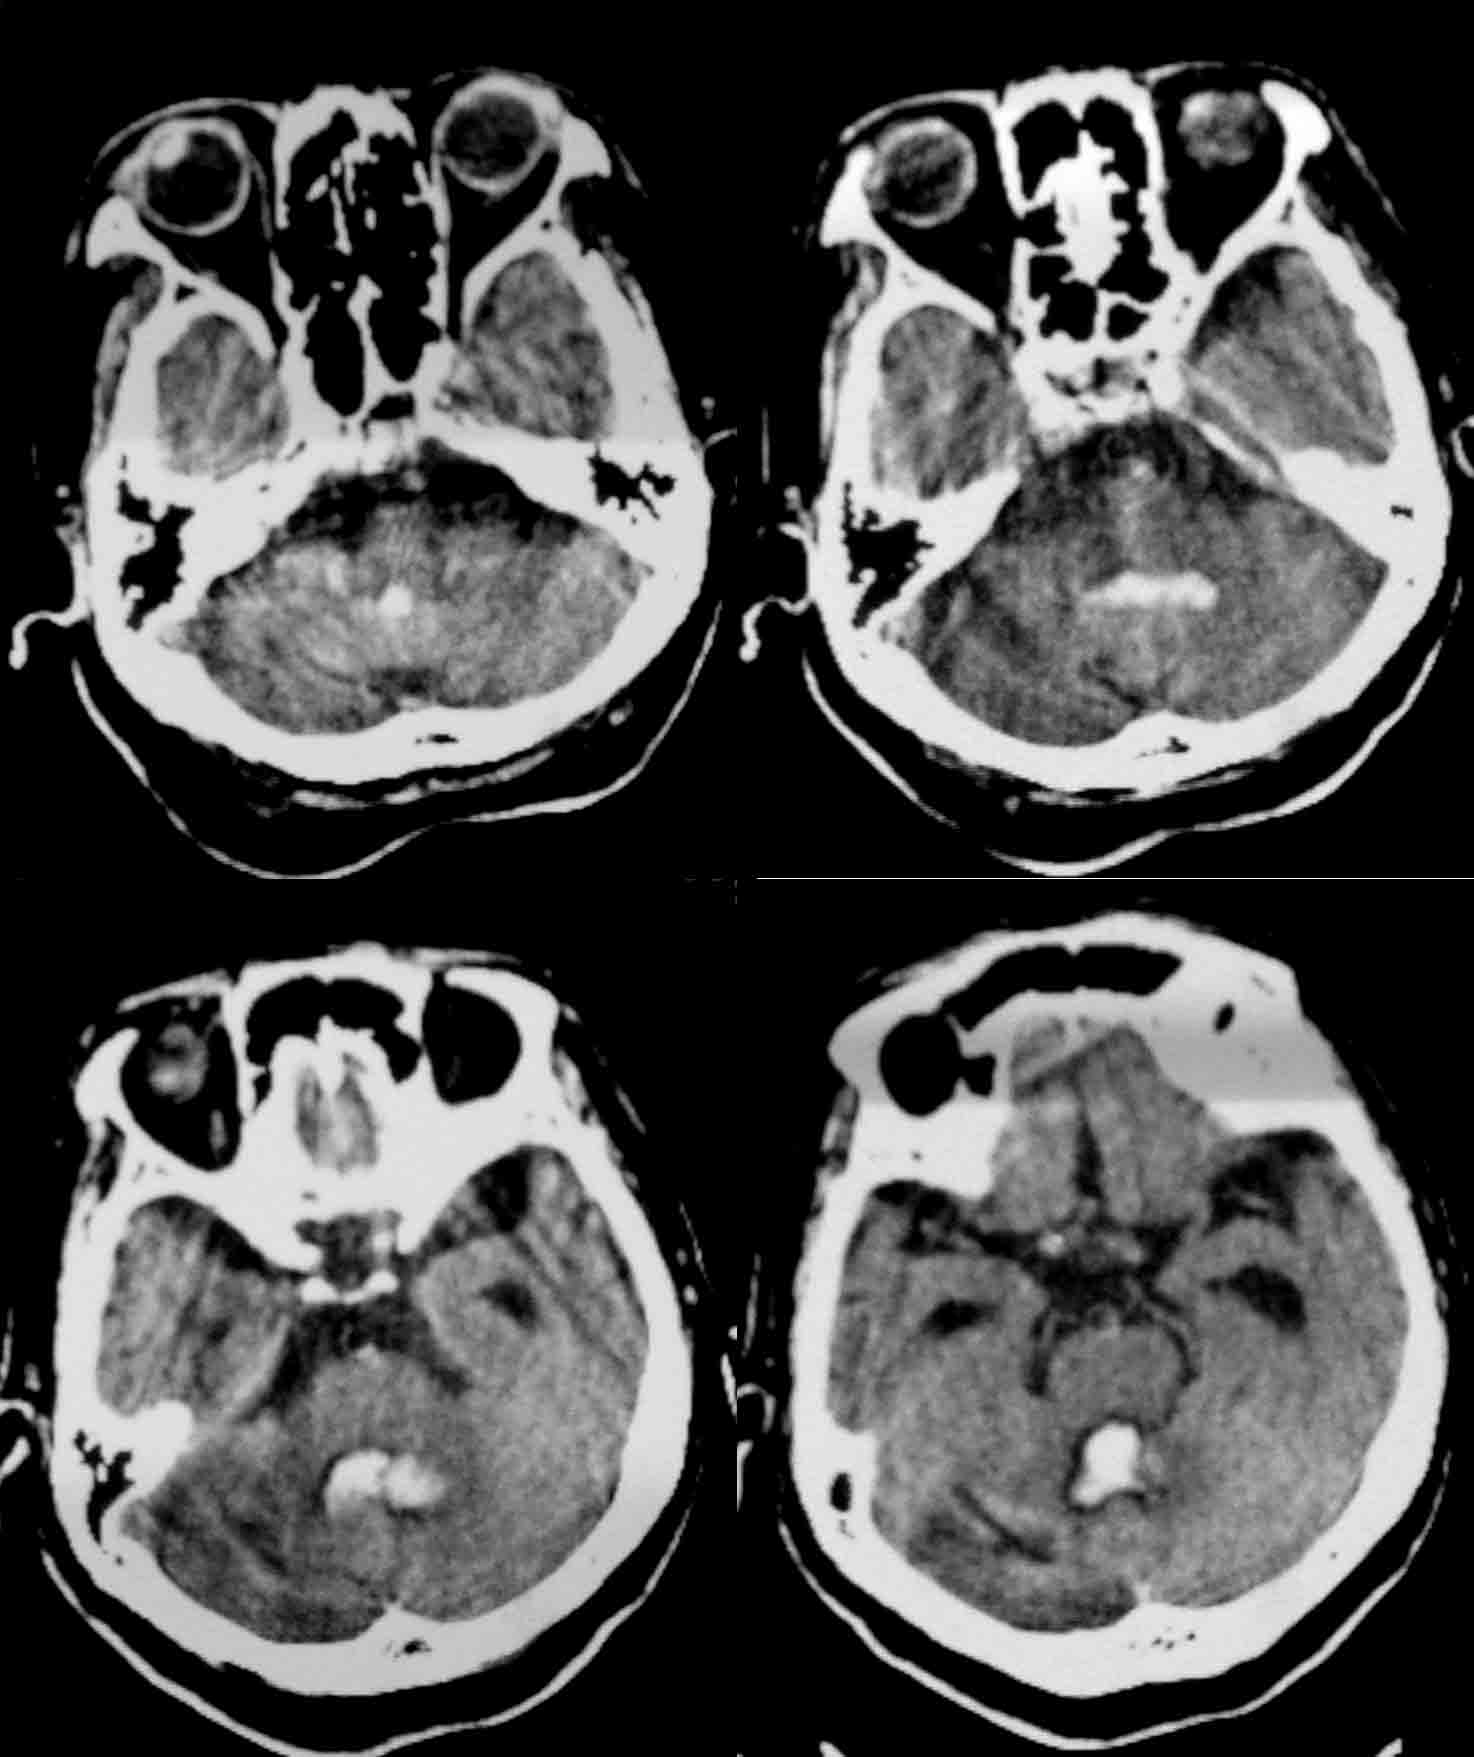

标题: CT24061:女86岁 头痛、呕吐1天 [打印本页]

女86岁 头痛、呕吐1天 请老师们看看,出血的位置是第三、四脑室出血吗?

应该是左侧小脑出血,破入脑室形成铸型。

1.左小脑齿状核出血破入脑室;

2.皮脑。

考虑:1.左小脑齿状核出血破入脑室;

2.脑白质稀疏症伴多发脑软化灶。

应该是左侧小脑出血,破入脑室形成铸型.皮层动脉硬化性脑病。

考虑:1.左小脑齿状核出血破入脑室;2.脑白质稀疏症伴多发脑软化灶。

1)左侧小脑出血破入脑室系统。2)多发性腔隙性脑梗塞。3)脑白质病。4)脑萎缩。